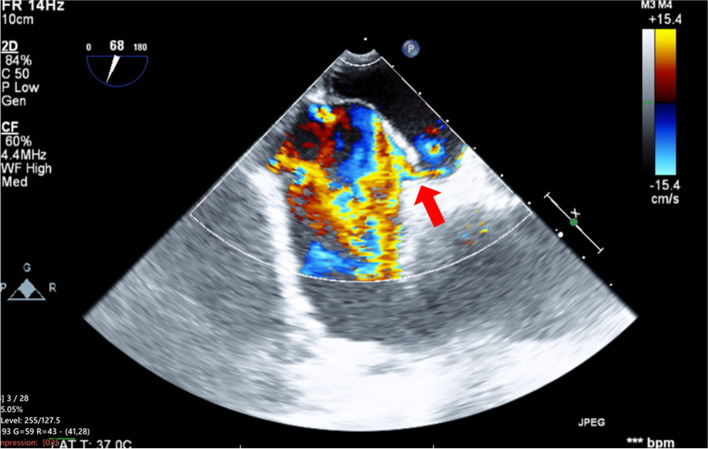

Case presentation: A 66-year-old man with interstitial pneumonia underwent OPCAB. Preoperative transesophageal echocardiography revealed right-to-left shunt flow through a PFO induced by the Valsalva maneuver. During OPCAB, heart displacement resulted in right-to-left shunting and acute hypoxemia, which quickly improved with increase of inspired oxygen fraction. After chest closure, bidirectional shunt flow developed under increased airway pressure.

Conclusions: Vigilant intraoperative monitoring with TEE and postoperative airway pressure management are important to address shunt flow and hypoxemia due to PFO.